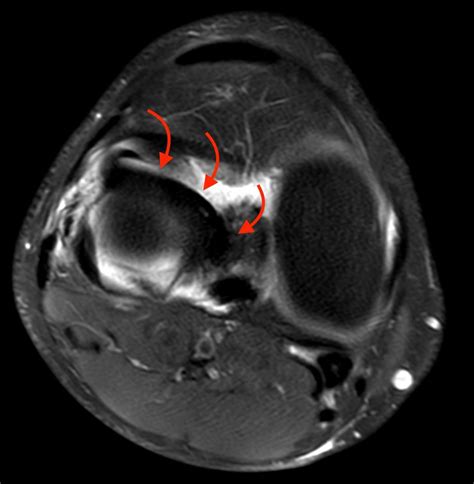

A bucket handle injury is a specific type of meniscal tear where the torn piece of the meniscus flips into the joint space, resembling the handle of a bucket. This type of tear is often more severe and can cause the knee to lock or give way. The meniscus is a C-shaped piece of cartilage that cushions the knee joint and helps distribute weight evenly. When it tears, it can lead to a range of symptoms that affect mobility and quality of life.

• Imaging Tests: X-rays, MRI, or CT scans may be ordered to visualize the meniscus and confirm the diagnosis. MRI is particularly useful for detecting meniscal tears and assessing the extent of the damage.